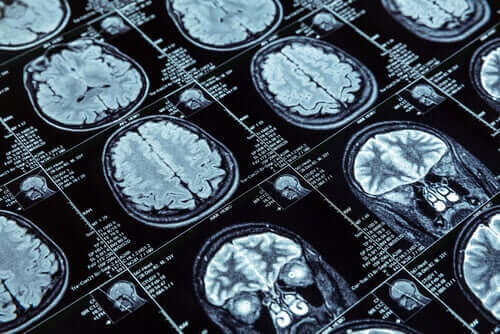

For å utføre forskningen, gjennomførte de kjernefysiske magnetiske resonanser på mer enn 600 mennesker i en alder av 45 år da bildetesten ble utført. Disse 600 personene var en del av en større gruppe som besto av mer enn 1000 mennesker. Forskerne fra New Zealand har studert disse menneskene siden barndommen.

De målte tykkelsen på hjernebarken og mengden grå substans gjennom resonansene de utførte på forskningsdeltakerne. Denne informasjonen tillot en sammenligning mellom de som viste antisosial atferd og de som ikke gjorde det.

Forskerne lærte viktige ting i den første gruppen. MR-undersøkelsene fra disse menneskene viste at, sammenlignet med de andre, krympet hjernebarken. I tillegg hadde de en litt mindre mengde med grå substans.

Det som er tydelig er endringen i hjernearkitekturen som en liten del av befolkningen kan ha, kanskje i forhold til antisosiale atferdstyper. Disse endringene kan forklare den antisosiale personligheten som vedvarende manifesterer opp gjennom årene.

For eksempel hadde tenåringer med antisosiale problemer endringer i frontal- og tinninglappen i hjernen. Noe som er mer alvorlig, er at voldelige fanger har mindre grå substans.

Forskere hadde vært på sporet av følelsesområdet i hjernen for å finne en assosiasjon. Forutsatt at antisosiale problemer skyldes mangel på empati, var det logisk å se etter endringer der. Resultatene indikerte at antisosiale tenåringer hadde en mindre hypofyse, og amygdalaen er området for empati.